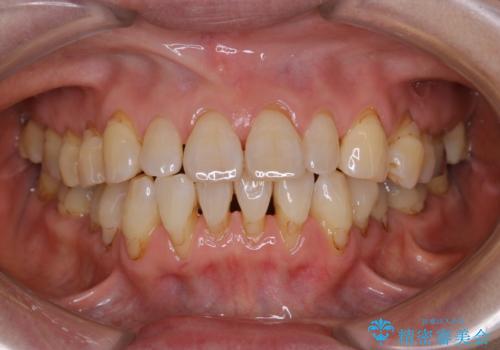

- クリーニングがかなり久しぶりで、全体的にきれいにして欲しいとのことで来院されました。全体的にステインの量がとても多かったため、施術前にご相談をし、60分コースでできる限りのステイン落としを行うこととなりました。今回は審美的に見える表側をメインでPMTCを行いました。

毎日丁寧に歯磨きをしていても、日常生活での飲食物などにより着色してしまうことはあります。PMTCでは、歯の表面の凸凹にミネラルを補給して、ツルツルの表面に仕上げます。定期的にPMTCを行うことにより、歯質の強化になり着色がつきにくい状態になります。